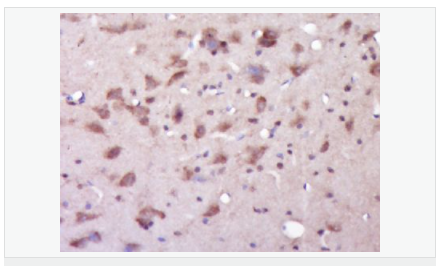

| 產(chǎn)品應用 | WB=1:500-2000 ELISA=1:5000-10000 IHC-P=1:100-500 IHC-F=1:100-500 Flow-Cyt=1ug/test IF=1:100-500 (石蠟切片需做抗原修復) not yet tested in other applications. optimal dilutions/concentrations should be determined by the end user. |

| 產(chǎn)品介紹 | Alzheimer's disease (AD) patients with an inherited form of the disease carry mutations in the presenilin proteins (PSEN1; PSEN2) or in the amyloid precursor protein (APP). These disease-linked mutations result in increased production of the longer form of amyloid-beta (main component of amyloid deposits found in AD brains). Presenilins are postulated to regulate APP processing through their effects on gamma-secretase, an enzyme that cleaves APP. Also, it is thought that the presenilins are involved in the cleavage of the Notch receptor, such that they either directly regulate gamma-secretase activity or themselves are protease enzymes. Several alternatively spliced transcript variants encoding different isoforms have been identified for this gene, the full-length nature of only some have been determined. [provided by RefSeq, Aug 2008] Function: Probable catalytic subunit of the gamma-secretase complex, an endoprotease complex that catalyzes the intramembrane cleavage of integral membrane proteins such as Notch receptors and APP (beta-amyloid precursor protein). Requires the other members of the gamma-secretase complex to have a protease activity. May play a role in intracellular signaling and gene expression or in linking chromatin to the nuclear membrane. Stimulates cell-cell adhesion though its association with the E-cadherin/catenin complex. Under conditions of apoptosis or calcium influx, cleaves E-cadherin promoting the disassembly of the E-cadherin/catenin complex and increasing the pool of cytoplasmic beta-catenin, thus negatively regulating Wnt signaling. May also play a role in hematopoiesis. Subunit: Homodimer. Component of the gamma-secretase complex, a complex composed of a presenilin homodimer (PSEN1 or PSEN2), nicastrin (NCSTN), APH1 (APH1A or APH1B) and PEN2. Such minimal complex is sufficient for secretase activity. Other components which are associated with the complex include SLC25A64, SLC5A7, PHB and PSEN1 isoform 3. Predominantly heterodimer of a N-terminal (NTF) and a C-terminal (CTF) endoproteolytical fragment. Associates with proteolytic processed C-terminal fragments C83 and C99 of the amyloid precursor protein (APP). Associates with NOTCH1. Associates with cadherin/catenin adhesion complexes through direct binding to CDH1 or CDH2. Interaction with CDH1 stabilizes the complex and stimulates cell-cell aggregation. Interaction with CDH2 is essential for trafficking of CDH2 from the endoplasmic reticulum to the plasma membrane. Interacts with CTNND2, CTNNB1, HERPUD1, FLNA, FLNB, MTCH1, PKP4 and PARL. Interacts through its N-terminus with isoform 3 of GFAP. Interacts with DOCK3. Subcellular Location: Endoplasmic reticulum membrane; Multi-pass membrane protein. Golgi apparatus membrane; Multi-pass membrane protein. Cell surface. Note=Bound to NOTCH1 also at the cell surface. Colocalizes with CDH1/2 at sites of cell-cell contact. Colocalizes with CTNNB1 in the endoplasmic reticulum and the proximity of the plasma membrane. Also present in azurophil granules of neutrophils. Tissue Specificity: Expressed in a wide range of tissues including various regions of the brain, liver, spleen and lymph nodes. Post-translational modifications: Heterogeneous proteolytic processing generates N-terminal (NTF) and C-terminal (CTF) fragments of approximately 35 and 20 kDa, respectively. During apoptosis, the C-terminal fragment (CTF) is further cleaved by caspase-3 to produce the fragment, PS1-CTF12. After endoproteolysis, the C-terminal fragment (CTF) is phosphorylated on serine residues by PKA and/or PKC. Phosphorylation on Ser-346 inhibits endoproteolysis. DISEASE: Defects in PSEN1 are a cause of Alzheimer disease type 3 (AD3) [MIM:607822]. AD3 is a familial early-onset form of Alzheimer disease. Alzheimer disease is a neurodegenerative disorder characterized by progressive dementia, loss of cognitive abilities, and deposition of fibrillar amyloid proteins as intraneuronal neurofibrillary tangles, extracellular amyloid plaques and vascular amyloid deposits. The major constituent of these plaques is the neurotoxic amyloid-beta-APP 40-42 peptide (s), derived proteolytically from the transmembrane precursor protein APP by sequential secretase processing. The cytotoxic C-terminal fragments (CTFs) and the caspase-cleaved products such as C31 derived from APP, are also implicated in neuronal death. Defects in PSEN1 are a cause of frontotemporal dementia (FTD) [MIM:600274]. Similarity: Belongs to the peptidase A22A family. SWISS: P49768 Gene ID: 5663 Database links: Entrez Gene: 5663 Human Entrez Gene: 19164 Mouse Omim: 104311 Human SwissProt: P49768 Human SwissProt: P49769 Mouse Unigene: 3260 Human Unigene: 998 Mouse Unigene: 44440 Rat Important Note: This product as supplied is intended for research use only, not for use in human, therapeutic or diagnostic applications. 此抗體識別分子量為45-50kDa早老素蛋白-1。PS-1主要在神經(jīng)細胞中表達,早老蛋白集中于體細胞和樹突狀細胞中。相反,再早發(fā)家族AD(FAD)中和散發(fā)AD病人中,PS1免疫反應出現(xiàn)在老年斑和神經(jīng)纖維纏結(jié)的神經(jīng)炎中。 |